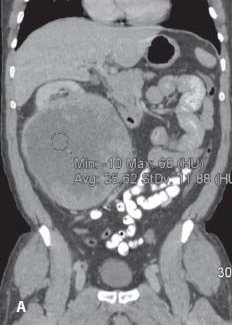

CT coronal image showing 18-cm right kidney mass.